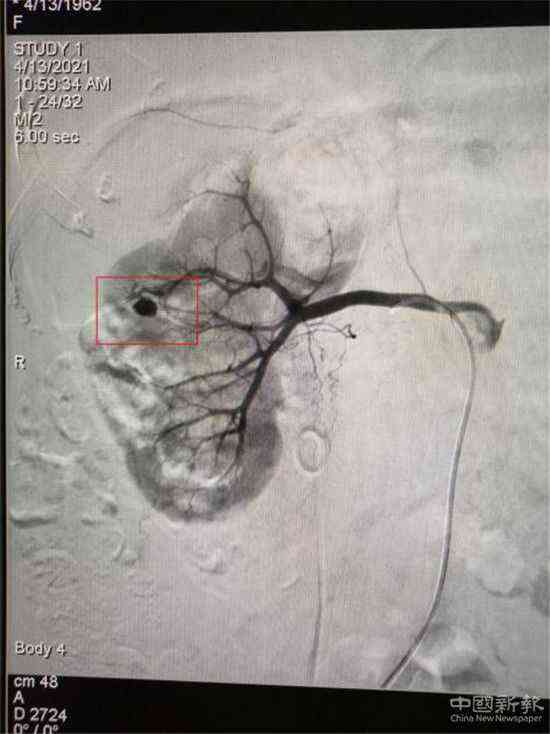

栓塞前造影圖(紅圈標(biāo)記為出血處)

家住湖南省郴州市嘉禾縣廣發(fā)鎮(zhèn)的鄧大媽,因患巨大腎結(jié)石進(jìn)行了“經(jīng)皮腎鏡取石術(shù)”,術(shù)后第3天出現(xiàn)大量鮮紅色血尿。經(jīng)過增強(qiáng)CT檢查,考慮為“腎穿刺口處動(dòng)脈出血”,醫(yī)院介入血管外科團(tuán)隊(duì)立即為患者在DSA下行“微創(chuàng)介入右腎出血?jiǎng)用}栓塞術(shù)”,術(shù)后出血立刻停止,尿液由紅色轉(zhuǎn)為正常顏色。